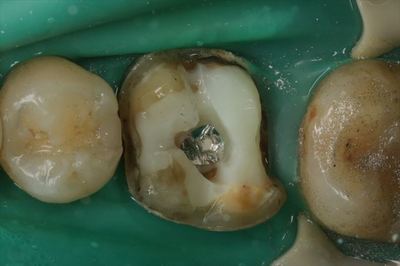

左下第一大臼歯ミラー像です。

とても黒変しています。

レントゲンにて内部がむし歯になっていることが判っています。

まずはメタルクラウンを除去しました。

金属を切削しますのでラバーダムを装着して切削片から粘膜を保護します。

白いレジン築造内の保持孔にメタルクラウン内面の突起が嵌合する構造でした。

切削が非常に容易でしたのでメタルコア用の銀合金で製作されたかぶせ物かもしれません。

そうであるとすれば、他の金属治療との間の電位差でガルバニ電流が流れ

黒くなっていることも頷けます。

いつものことながら周囲から内部が汚染されています。

取れていないことと問題ないことはイコールではないことが判ります。

レジン築造を取り除いていくと遠心部分の重度のむし歯がレントゲン通り姿を現しました。

軟化象牙質(=むし歯)を染める う蝕検知液で染色し水洗しました。

かなりの範囲が染まっています。

取れていなくて痛くなくてもこのような状況になっていることがあります。